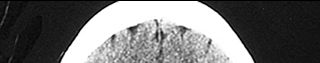

Can you identify the area of his brain that was affected?